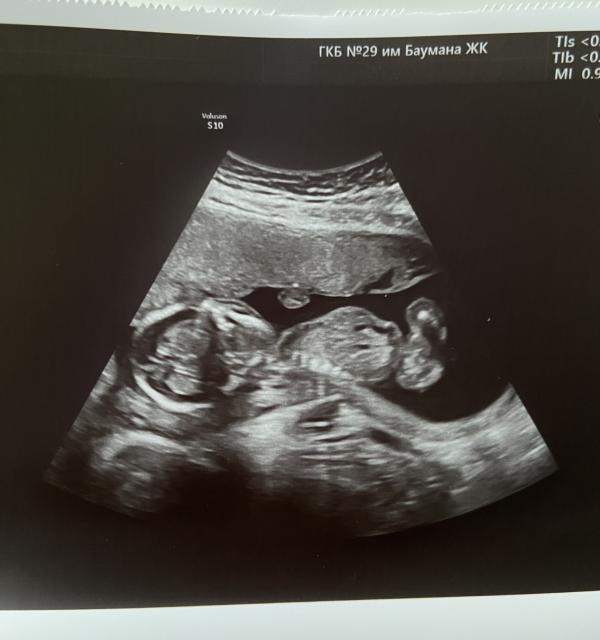

Первое фото нашего малыша 🥰 16 недель. Ножки поджал , спит наверное 🥹

Это фото сделали когда на осмотре в ЖК шейку матки измеряли.